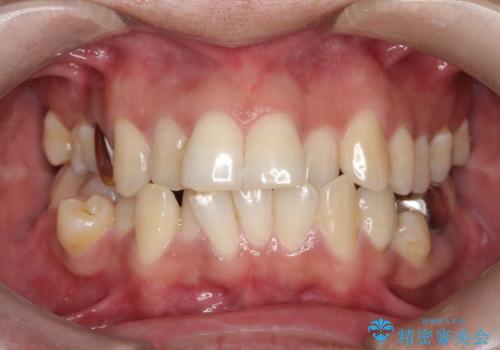

【インビザライン】笑ったときに目立つ八重歯をなおしたい

- 笑ったときに八重歯が見えることを主訴に来院されました。

下の前歯が一本足りない患者様でしたので、シミュレーションを作り、事前に患者様と治療ゴールのイメージをしっかり共有したうえでインビザラインを用いて治療を行っています。

奥歯を後ろのほうに動かすことで、前歯も少し下がることができ、矯正後の口元も満足していただきました。